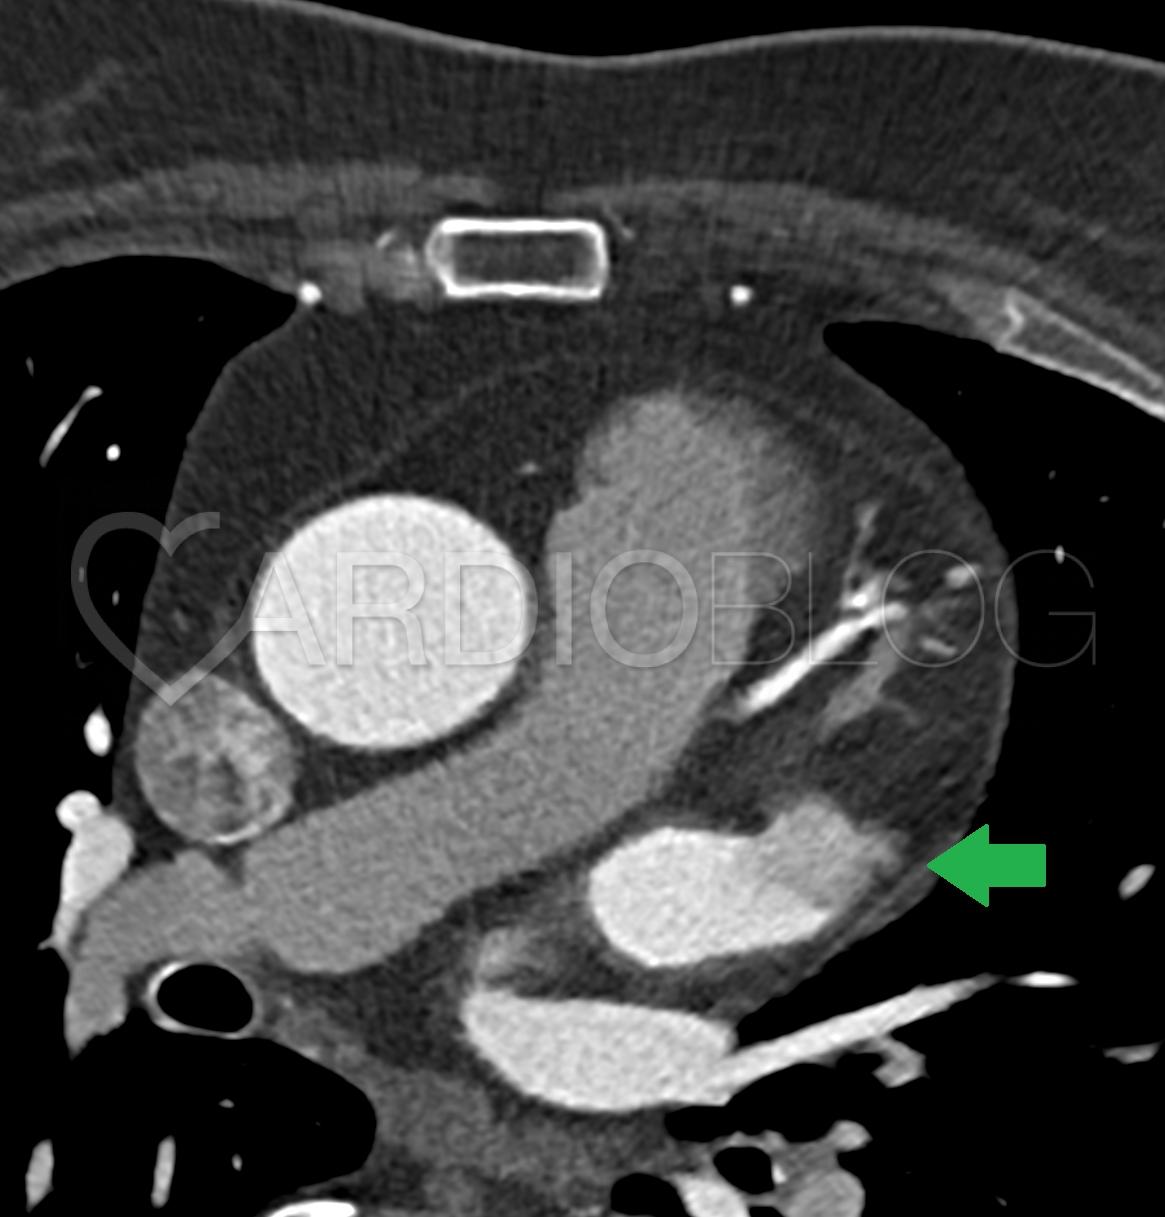

<p>A beteget otthonába bocsájtották, majd közel 2 évvel később atípusos mellkasi fájdalom, terhelésre jelentkező vállfájdalom, hányinger és többszöri adekvát ICD sokk miatt kontroll koronária CT angiográfiát végeztünk (2. kép).</p>

<p style="text-align: center;"><strong><a href="http://www.cardioblog.hu/wp-content/uploads/Marfan2.jpg" target="_blank"><img class="aligncenter size-large wp-image-2656" title="Marfan2" src="http://www.cardioblog.hu/wp-content/uploads/Marfan2-704x405.jpg" alt="" width="700" height="402" /></a></strong></p>

<p><strong><em>2. Kép:</em></strong><em> A műérre felvarrt jobb koszorúér és bal főtörzs szájadékában egyaránt súlyos fokú, preokkluzív szűkület ábrázolódott (zöld nyilak). </em></p>